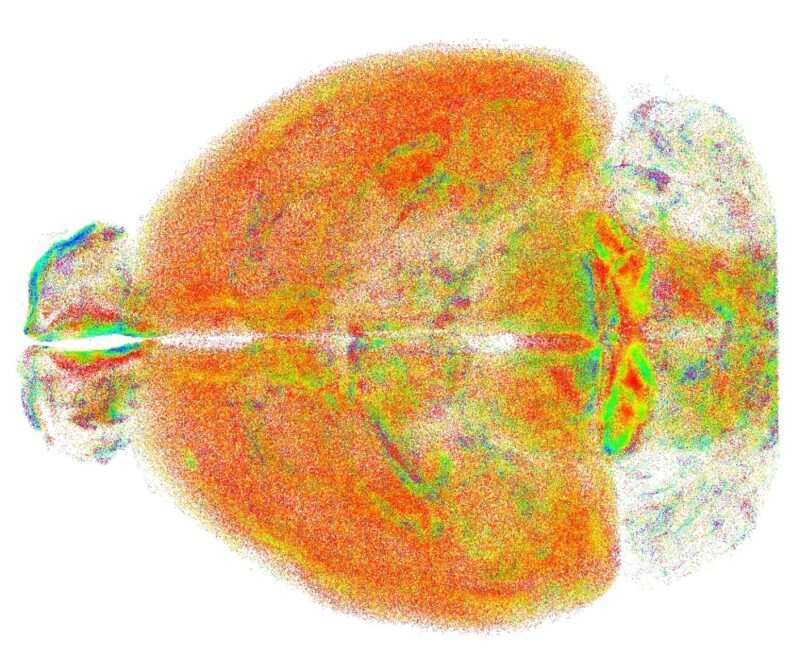

La nuova tecnica elaborata dai ricercatori, chiamata RAPID (acronimo di Rapid Autofocus via Pupil-split Image phase Detection) propone una nuova integrazione della microscopia a foglio di luce, capace di correggere in tempo reale i disallineamenti introdotti dal campione, consentendo di visualizzare e rappresentare interi cervelli di modelli murini con risoluzione subcellulare.

L'alta risoluzione garantita da RAPID – che è anche oggetto di un brevetto internazionale di cui sono titolari Unifi, Lens e Cnr - ha permesso ai ricercatori di studiare su scala dell'intero cervello problematiche finora analizzate solo in piccole aree circoscritte. Si è indagata, ad esempio, la distribuzione spaziale di un particolare tipo di neuroni – che esprimono somatostatina – mostrando come queste cellule tendono ad organizzarsi in cluster spaziali, che si sospetta rendano più efficace la loro azione inibitoria.

Un'altra applicazione riguarda la microglia, un insieme di cellule con diverse funzioni (dalla risposta ad elementi patogeni alla regolazione della plasticità dei neuroni), la cui forma cambia a seconda del ruolo che svolgono. L'analisi della microglia effettuata con RAPID ha evidenziato differenze significative tra varie regioni del cervello, aprendo la strada a nuovi studi sul ruolo di questa popolazione cellulare.